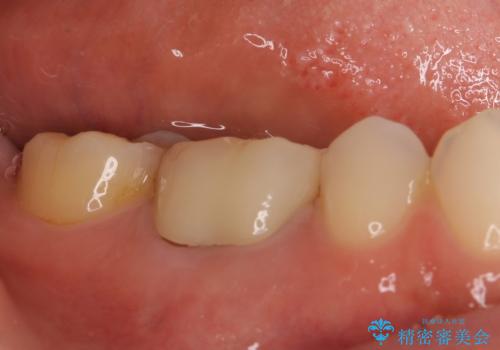

根管治療を行った奥歯は、再発防止や残された歯質を守るため、クラウンによる補綴治療が必要となります。

補綴後6か月経過しレントゲンを撮影したところ、根尖周辺の病変が消失していることが確認できました。